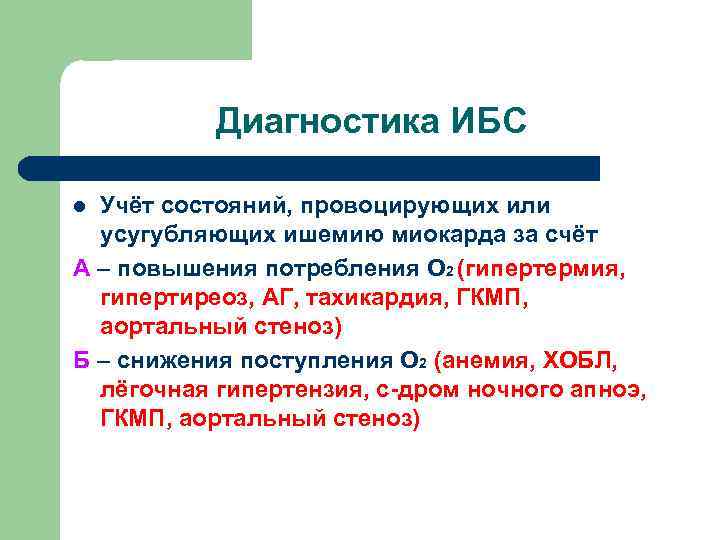

Диагностика ИБС Учёт состояний, провоцирующих или усугубляющих ишемию миокарда за счёт А – повышения потребления О 2 (гипертермия, гипертиреоз, АГ, тахикардия, ГКМП, аортальный стеноз) Б – снижения поступления О 2 (анемия, ХОБЛ, лёгочная гипертензия, с-дром ночного апноэ, ГКМП, аортальный стеноз) l